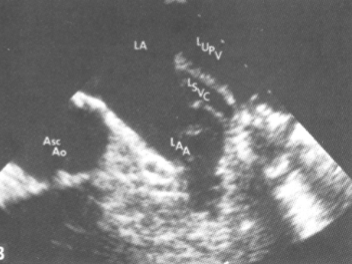

Persistent Left Superior Vena Cava

most common congenital anomaly that affects the systemic veins

The LSVC drains into the Coronary Sinus for blood to return to the RA

No tx is necessary

No complications

Where should contrast be injected in order to diagnose a persistent lt SVC?

Left arm

Persistent Left SVC:

dilated Coronary Sinus

May follow vessel

May mimic:

Pericardial effusion

Anomalous pulmonary venous return

Descending aorta